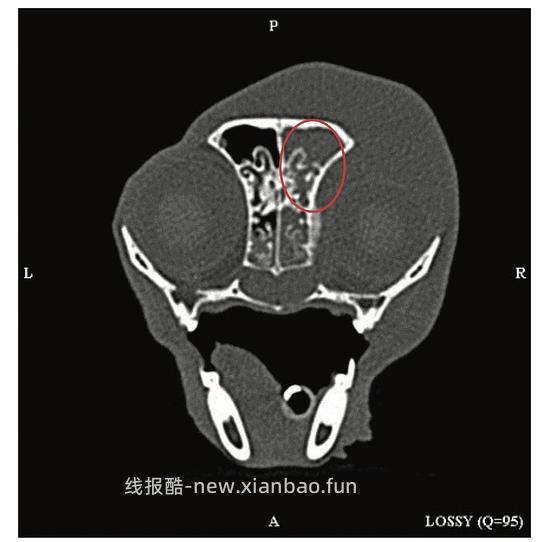

淋巴瘤是猫鼻腔最常见的肿瘤(占猫鼻腔肿瘤的50%,其他鼻腔肿瘤包括腺癌、鳞状细胞癌及纤维肉瘤等),常见于年龄较大、FeLV阴性的猫。[29, 38]一项研究显示,经鼻活检诊断出的淋巴瘤中,约50%为大淋巴细胞,40%为中~小细胞,10%左右为混合细胞。[40]鼻内病变最有效的识别技术是头部CT检查,如图11所示,除鼻腔外还可同时筛查可能受累的咽后淋巴结。此外,理想情况下应进行细胞学和组织学评估。

图11猫鼻腔淋巴瘤CT影像,显示右侧鼻腔及同侧软组织区域(红圈内)存在软组织密度影[29]

鼻腔淋巴瘤的预后尚可至良好,报道MST在12-30月不等。它通常是一种局部性疾病:10-37%的死亡(安乐)归因于局部复发;10-33%归因于全身性进展。据报道,在疾病进展的病例中,肾脏是常见的远端转移部位。[29]作为一种孤立且且对放射敏感的肿瘤,其治疗通常基于放疗/化疗或两者联合,目前尚无法确定最有效的治疗方案。在一项研究中,最长MST=955days是通过联合使用放疗化疗获得的。因此,目前普遍认为:对于局部病变的患者,单独使用放疗即可实现长期生存;对于有证据或怀疑存在全身系统性淋巴瘤的患者,则适合联用或单独化疗的方案,当然,涉及到个体差异,最终采取的方案不同。[29, 38]